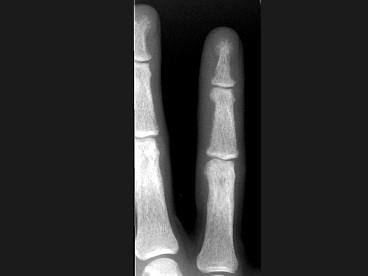

女,41岁,慢性肾功能不全,结合图像,最可能的诊断是?(?)A.白血病B.甲状旁腺功能亢进C.地中海贫血D.镰状细胞贫血E.骨关节结核

问题 女,41岁,慢性肾功能不全,结合图像,最可能的诊断是?(?)

选项 A.白血病 B.甲状旁腺功能亢进 C.地中海贫血 D.镰状细胞贫血 E.骨关节结核

答案 B